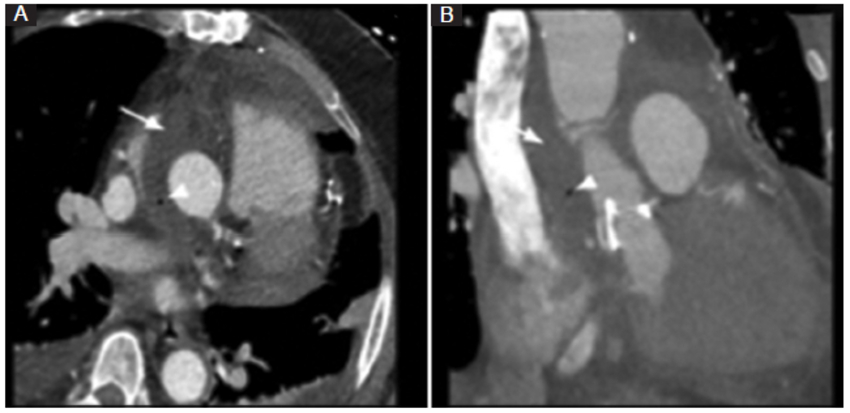

Cirugía de Wheat

El empleo de un injerto aórtico ascendente que se coloca distal al ostium de las arterias coronarias se conoce como injerto supracoronario, y al asociarse con un reemplazo de la válvula aórtica se conoce como técnica de Wheat (Fig. 1). Los injertos supracoronarios se indican en pacientes con aneurisma de aorta torácica ascendente (generalmente de origen aterosclerótico) que presentan indemnidad estructural de los senos de Valsalva. Con este procedimiento se evitan las complicaciones de la manipulación del ostium coronario nativo, lo cual se traduce en una minimización de los riesgos de pseudoaneurismas, estenosis, trombosis y pliegues en el sitio de la anastomosis coronaria. Las complicaciones más frecuentes de este procedimiento son la disección aórtica nativa proximal y los pseudoaneurismas2,3,4.